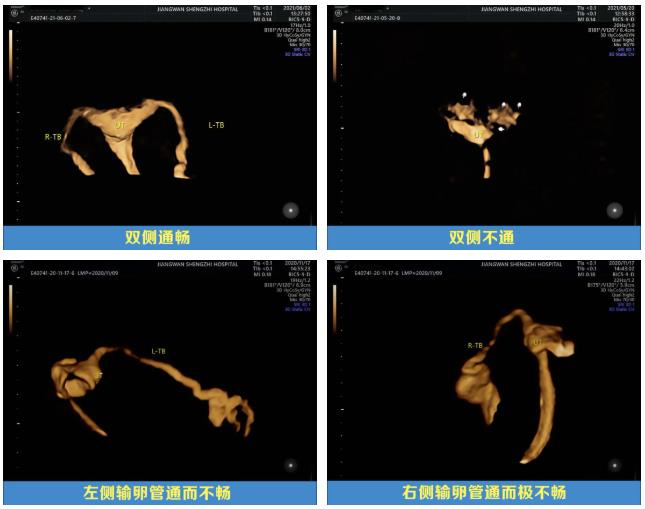

引起女性不孕因素主要有输卵管因素、盆腔因素、卵巢因素、免疫因素、精神因素以及子宫因素等,输卵管因素是女性不孕症的较常见的原因,输卵管阻塞、通而不畅或输卵管功能不良造成的不孕约占25~35%,因此输卵管通畅度检验是女性不孕检查的重要步骤。

1.了解输卵管通畅程度及其形态、阻塞部位;

长沙江湾妇产医院超声影像科团队运用GE-E10四维彩超,根据临床需求为患者制定个性化超声方案,可对包括子宫、输卵管、卵巢在内的女性生殖系统或盆腔相关的常见不孕原因进行系统性精准筛查,找出病因,对症治疗,并将其安全、无创、精准、便捷、经济的特点发挥到极致!